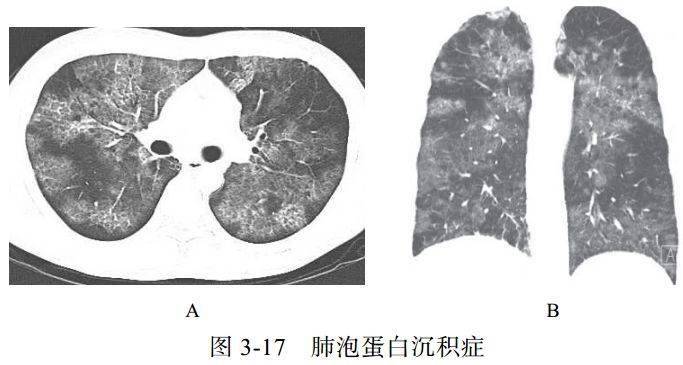

(三)肺泡蛋白沉积症

肺泡蛋白沉积症(PAP)是一种比较罕见的肺部慢性疾病,分为先天性、自身免疫性及继发性,自身免疫性 PAP 多见。镜下观察细支气管和肺泡内含大量过碘酸-希夫(PAS)染色阳性的富磷脂细微颗粒,肺泡壁及间质结构正常,小叶间隔增厚。临床表现轻于影像学表现,最常见症状是气短,特别是活动后明显,部分患者的病情可自行缓解,但可复发

影像学表现

(1)磨玻璃样影,与正常肺组织边界清楚,其边缘呈多角形或多边形,呈地图状分布(图 3-17)

(2)弥漫细线及网格影,代表小叶内及小叶间隔增厚,磨玻璃样影及小叶间隔增厚叠加形成铺路石征或碎石路征

(3)气腔实变,可见含气支气管征

(4)肺间质纤维化表现为蜂窝肺及牵拉性支气管扩张,出现此表现提示预后不良

(5)纵隔、肺门淋巴结肿大少见